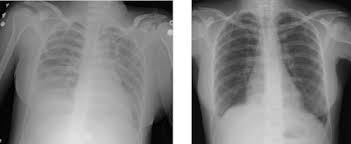

- आपके फेफड़ों में तरल पदार्थ को मापने के लिए छाती का एक्स-रे।

तीव्र श्वसन संकट सिंड्रोम (ARDS) फेफड़ों की एक चोट है जो तब उत्पन्न होती है जब आपके फेफड़ों में छोटी वायु थैलियों (एल्वियोली) में तरल पदार्थ जमा हो जाते हैं । ARDS आपके फेफड़ों को हवा से भरने से रोकता है और आपके रक्त में ऑक्सीजन के स्तर को खतरनाक रूप तक कम कर देता है (हाइपोक्सिया)।

तीव्र श्वसन संकट सिंड्रोम (एआरडीएस) की स्थिति तब उत्पन्न होती है जब आपके फेफड़ों की छोटी वायु थैलियों में तरल पदार्थ जमा हो जाता है और इसके चलते ऑक्सीजन का स्तर गंभीर रूप से कम हो जाता है।